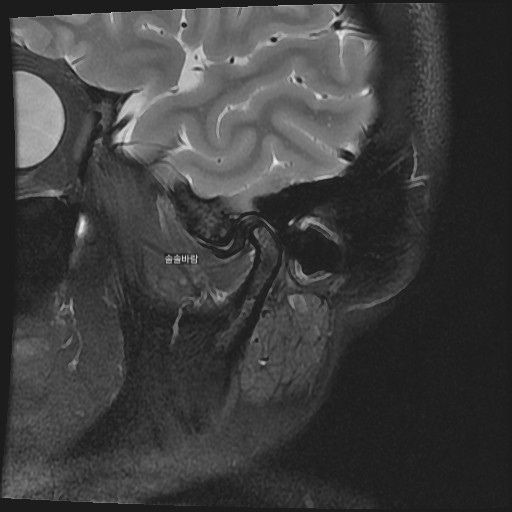

구강내과 턱 MRI 어느 사진이 우측? 좌측?인지 어떻게 보나요? 디스크 두꺼워짐 심한가요?ㅜ

구강내과 턱 MRI 사진 보는데 귀 위치가 다 똑같아서요

어느 사진이 우측? 좌측?인지 어떻게 보나요?

그리고 사진 상 디스크 두꺼워짐 심한가요?ㅜ

현재 사진만으로는 정확히 왼쪽이나 오른쪽이다 라고 할 수 없습니다. 이는 데이터 상의 reference가 필요하며 보통은 해당 부위가 질문자님 기준으로 좌측일 가능성이 가장 크나 이는 좌우 반전을 할 수 있기 때문에 무조건 좌측이라고 할 수 없습니다. 현재 개구시와 폐구시에 보았을 때 condyle (아래턱 부위의 일부)가 disc를 넘어가지 못하고 있으며 이러한 경우 개구제한이 있거나 넘어가더라도 소리가 나면서 넘어갈 수 있습니다. 일부 염증도 보이고 있으므로 내과적인 치료를 하셔야 할 것으로 보입니다.